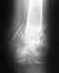

Вы показываете не в "чуть согнутом" положении, а в почти разогнутом. Он не дает информации об амплитуде движений и препятствиях движениям.

Еще раз: профильные снимки надо сделать 1) в максимальном сгибании и 2) в максимальном разгибании в локте.